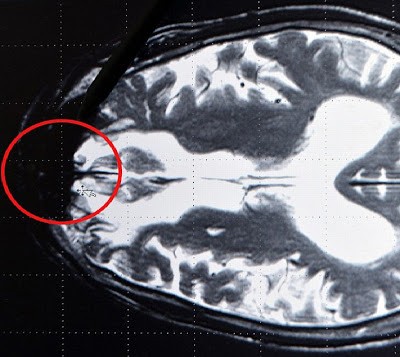

قام البروفيسور (جيرهارد روث) أستاذ طب الأعصاب بجامعه (بريمن) الألمانية , العالم الألماني الأكثر شهره في أبحاثجينات الأدمغة بإظهار أبحاث تؤكد بعض الدراسات السابقة حيث أعلن إكتشافه ماقام بتسميته (بقعه سوداء) في الدماغ وهي ماتجعل الشخص (مريض الشيطان) حسب تعبيره , وهو جزء معين يقوم بضخ الأفكار الشريرة التي تجعل من صاحبها يتربّص بالشر لكل من حوله بمجرد أن تنشط هذه البقعه السوداء بأي نشاط سلبي حيث تقوم فورا بتوليد جميع المحرّضات على السلوك الإجرامي والعنيف , فهو مركز إصدار القرارات جميعها.

وقد قام جيرهارد بعرض شريط فيديو تظهر فيه أعمال عنف وحشية على مجرمين ارتكبوا أعمال إجراميه متنوعه واحدا تلو الآخر وقياس أنشطتهم الدماغيه والكشف عليها بالأشعه السينية , فوجد أن جميع أجزاء الدماغ تتفاعل مع ماترى إلا جزء واحد بقي راكدا بلا أي تفاعل , ورغم وجود هذا الجزء الذي سماه البقعه السوداء والذي تم تداوله إعلاميه بإسم وكر الشيطان , أي المركز الذي يصدر الاوامر الشريرة لدى الإنسان.